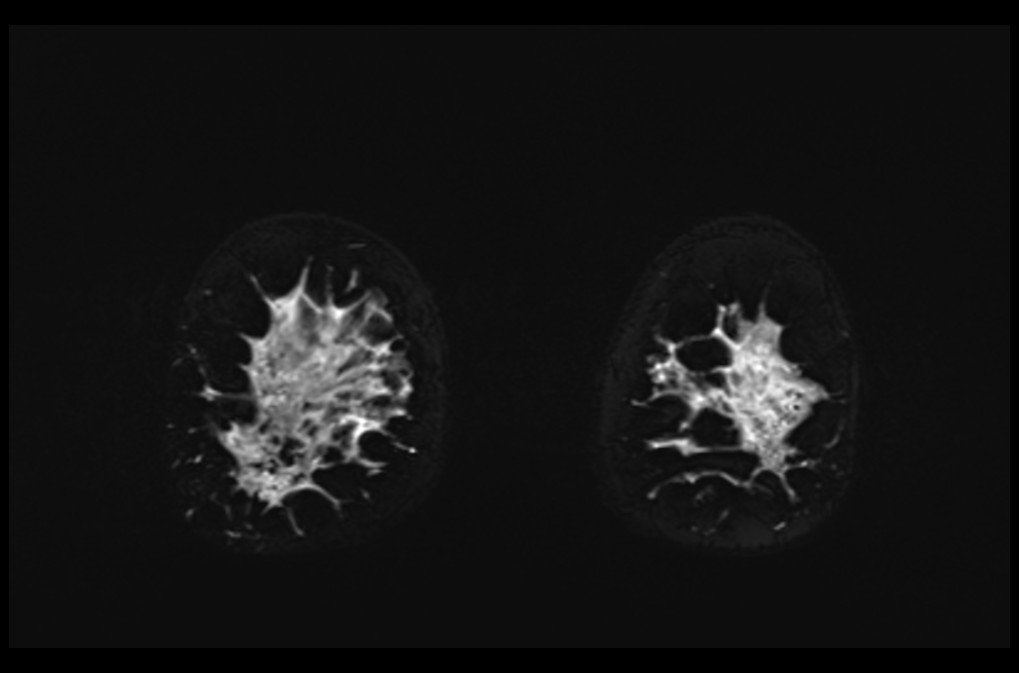

MRI breast implant stir coronal images 3 - MRI